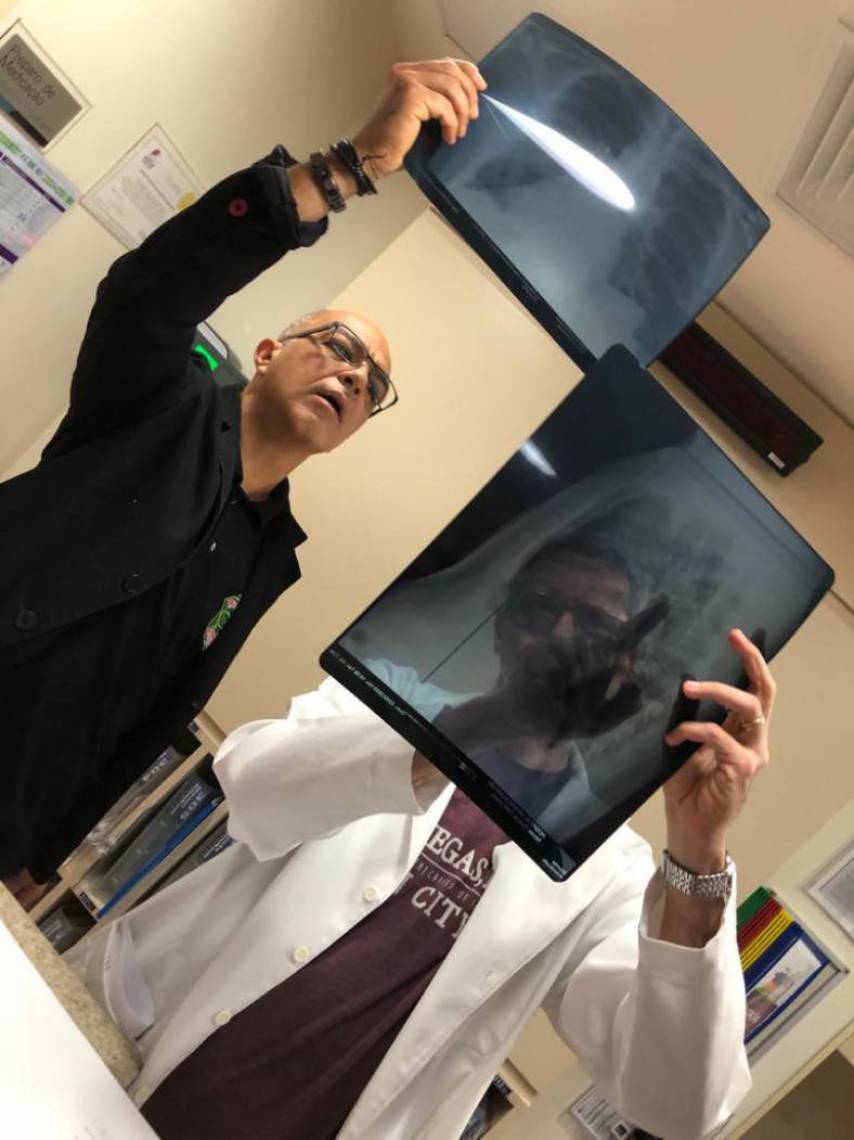

O senador licenciado Cid Gomes (PDT) passou por exame realizado pela Perícia Forense (Pefoce), por ter sido levantado rumor de que o tiro teria sido de bala de borracha. A irmã do senador, Lia Gomes, enviou fotos do exame com detalhe da lesão sofrida por ele.

O senador segue internado no hospital Monte Klinikum, em Fortaleza, após ter sido atendido no Hospital do Coração de Sobral. Segundo o último boletim médico do Monte Klinikum, Cid Gomes teve trauma torácico por arma de fogo, que ocasionou perfuração do hemotórax esquerdo, lesão pulmonar e pneumotórax hipertensivo, segundo o boletim médico do Monte Klinikum.